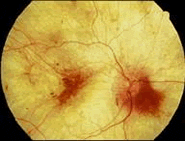

| Figura 3. CDM: Atrofia de la retina deja ver el pigmento y la esclera con sus vasos en un patrón llamado de “sal y pimienta”. | Figura 4. CDM: Estadio terminal de la atrofia de la retina y coroides confiere la apariencia blanca del fondo de ojo y permite observar la esclera desnuda. |

COROIDEREMIA (CDM): Es una entidad hereditaria causada en los hombres por mutación en el cromosoma X (X linked disorder) del gen que codifica la proteína Rab escolta 1. La Rab escolta 1 participa en las modificaciones covalentes de proteínas involucradas en el transporte de vesículas en las células. Las mujeres –que son portadoras- llevan el gen como en el caso de la hemofilia y son asintomáticas o por lo general sólo levemente sintomáticas. Se caracteriza por perdida de visión progresiva desde edad temprana con nictalopía inicial y luego por constricción de los campos visuales. Las manifestaciones neuro-psiquiátricas incluyen ENFERMEDAD MENTAL no específica, ataxia, paraparesis, epilepsia, distonia cervical y NISTAGMUS. Matsuyama reportó un paciente con CDM, deficiencia parcial de la aril sulfatasa A y leucodistrofia, la cual no se pudo comprobar en este paciente. La CDM se puede diagnosticar clínicamente por la historia y la apariencia del fondo del ojo. Los electro-retinogramas documentan el deterioro de los foto-receptores, de las células bipolares y de las células de Müller, en forma de reducción acelerada en la amplitud de los potenciales. La prueba sérica comprueba ausencia de anticuerpos contra la proteína Rab escolta 1. La proteína en mención esta presente en todas las capas de la retina a través del desarrollo. Su concentración y su agregación selectiva en las capas aumenta con el paso del tiempo, en contraste a otras proteínas coexistentes (Figuras 1 y 2). Los cambios patológicos intraoculares son obvios al examen fundoscópico, hasta que se llega a la atrofia retiniana “terminal”. (Figuras 3 y 4). El síndrome XYY en este sujeto no tuvo repercusión sobre sus síntomas. La anomalía XYY es poco común .Se manifiesta en varones altos y delgados de inteligencia a veces subnormal que además pueden tener exostosis, criptorquidia, oligospermia y acné Rara vez exhiben conducta autista o antisocial. Si tienen cataratas se debe sospechar comorbilidad con distrofia muscular miotónica.